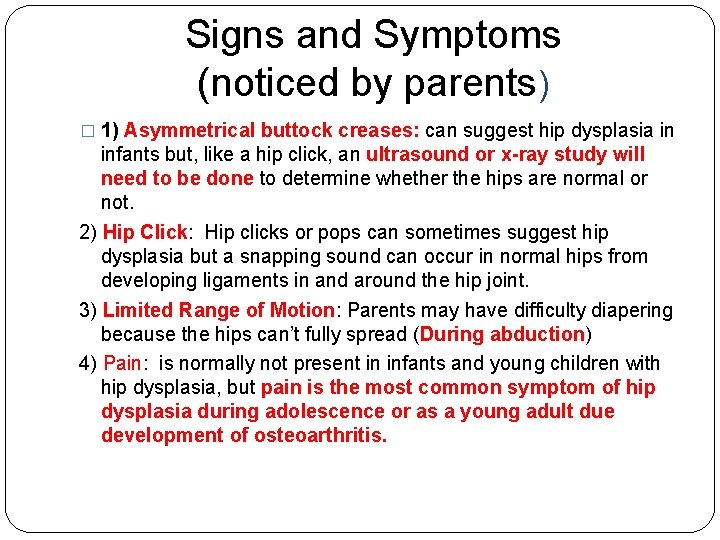

Signs and Symptoms (noticed by parents) � 1) Asymmetrical buttock creases: can suggest hip dysplasia in infants but, like a hip click, an ultrasound or x-ray study will need to be done to determine whether the hips are normal or not. 2) Hip Click: Hip clicks or pops can sometimes suggest hip dysplasia but a snapping sound can occur in normal hips from developing ligaments in and around the hip joint. 3) Limited Range of Motion: Parents may have difficulty diapering because the hips can’t fully spread (During abduction) 4) Pain: is normally not present in infants and young children with hip dysplasia, but pain is the most common symptom of hip dysplasia during adolescence or as a young adult due development of osteoarthritis.